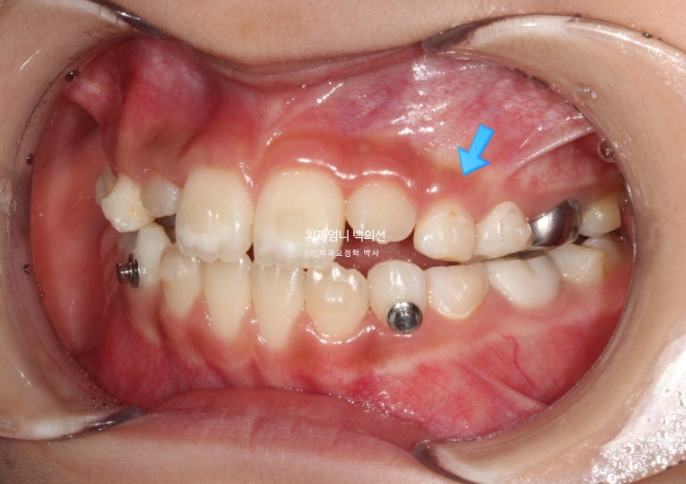

중심선이 많이 어긋나 있으며 파란화살표는 위아래가 거꾸로 물리는 반대교합입니다.

악궁확장으로 파란 화살표 반대교합이 해소가 되면서 교합간섭이 사라졌습니다.

아래 붙어있는 메탈 고리는 고무줄 거는 고리입니다.

교합간섭이 사라지니 턱이 제 위치를 찾으며 어긋났던 앞니 중심선도 자연스레 맞아졌습니다.